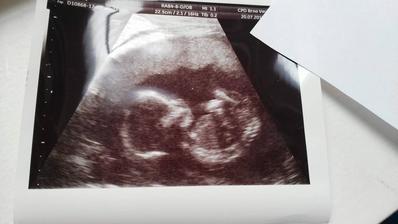

24.5. 2017 kontrolní ultrazvuk. Jsi krásný medvídek a srdíčko tluče překrásně